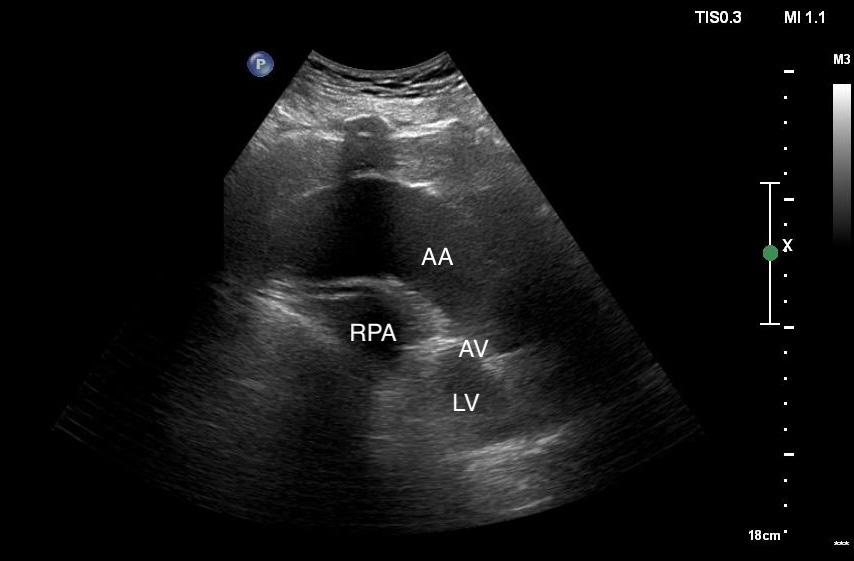

In the case covered in this article, an 85-year-old man with septic shock caused by a perforated sigmoid colon was profoundly hypovolemic and required crystalloid resuscitation and dual vasopressors. Ultrasound revealed that his internal jugular vessels were completely collapsible. Initial attempts to place the catheter were unsuccessful due to vessel collapse. The Trendelenburg position did not adequately dilate the internal jugular vein, as shown in Image 1. However, using a passive leg raise, significant dilation of the internal jugular vein was observed, enabling successful cannulation (Image 2).